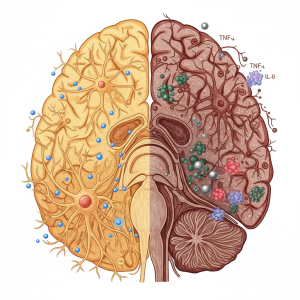

– تقویت التهاب میکروگلیال: کمبود ویتامین D منجر به فعالسازی میکروگلیا و آزادسازی سیتوکاینهای التهابی (IL‑۶، TNF‑α) میشود که اثر سموم را چندبرابر میکند.